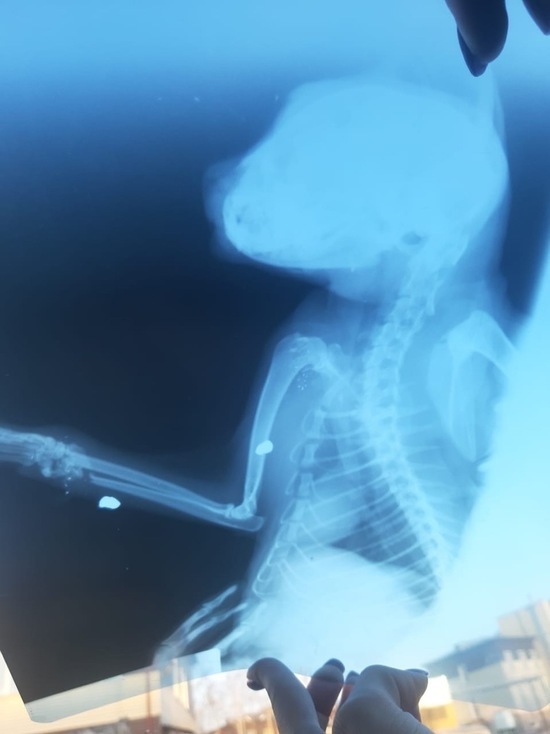

Рентгеновские снимки: изучаем животных